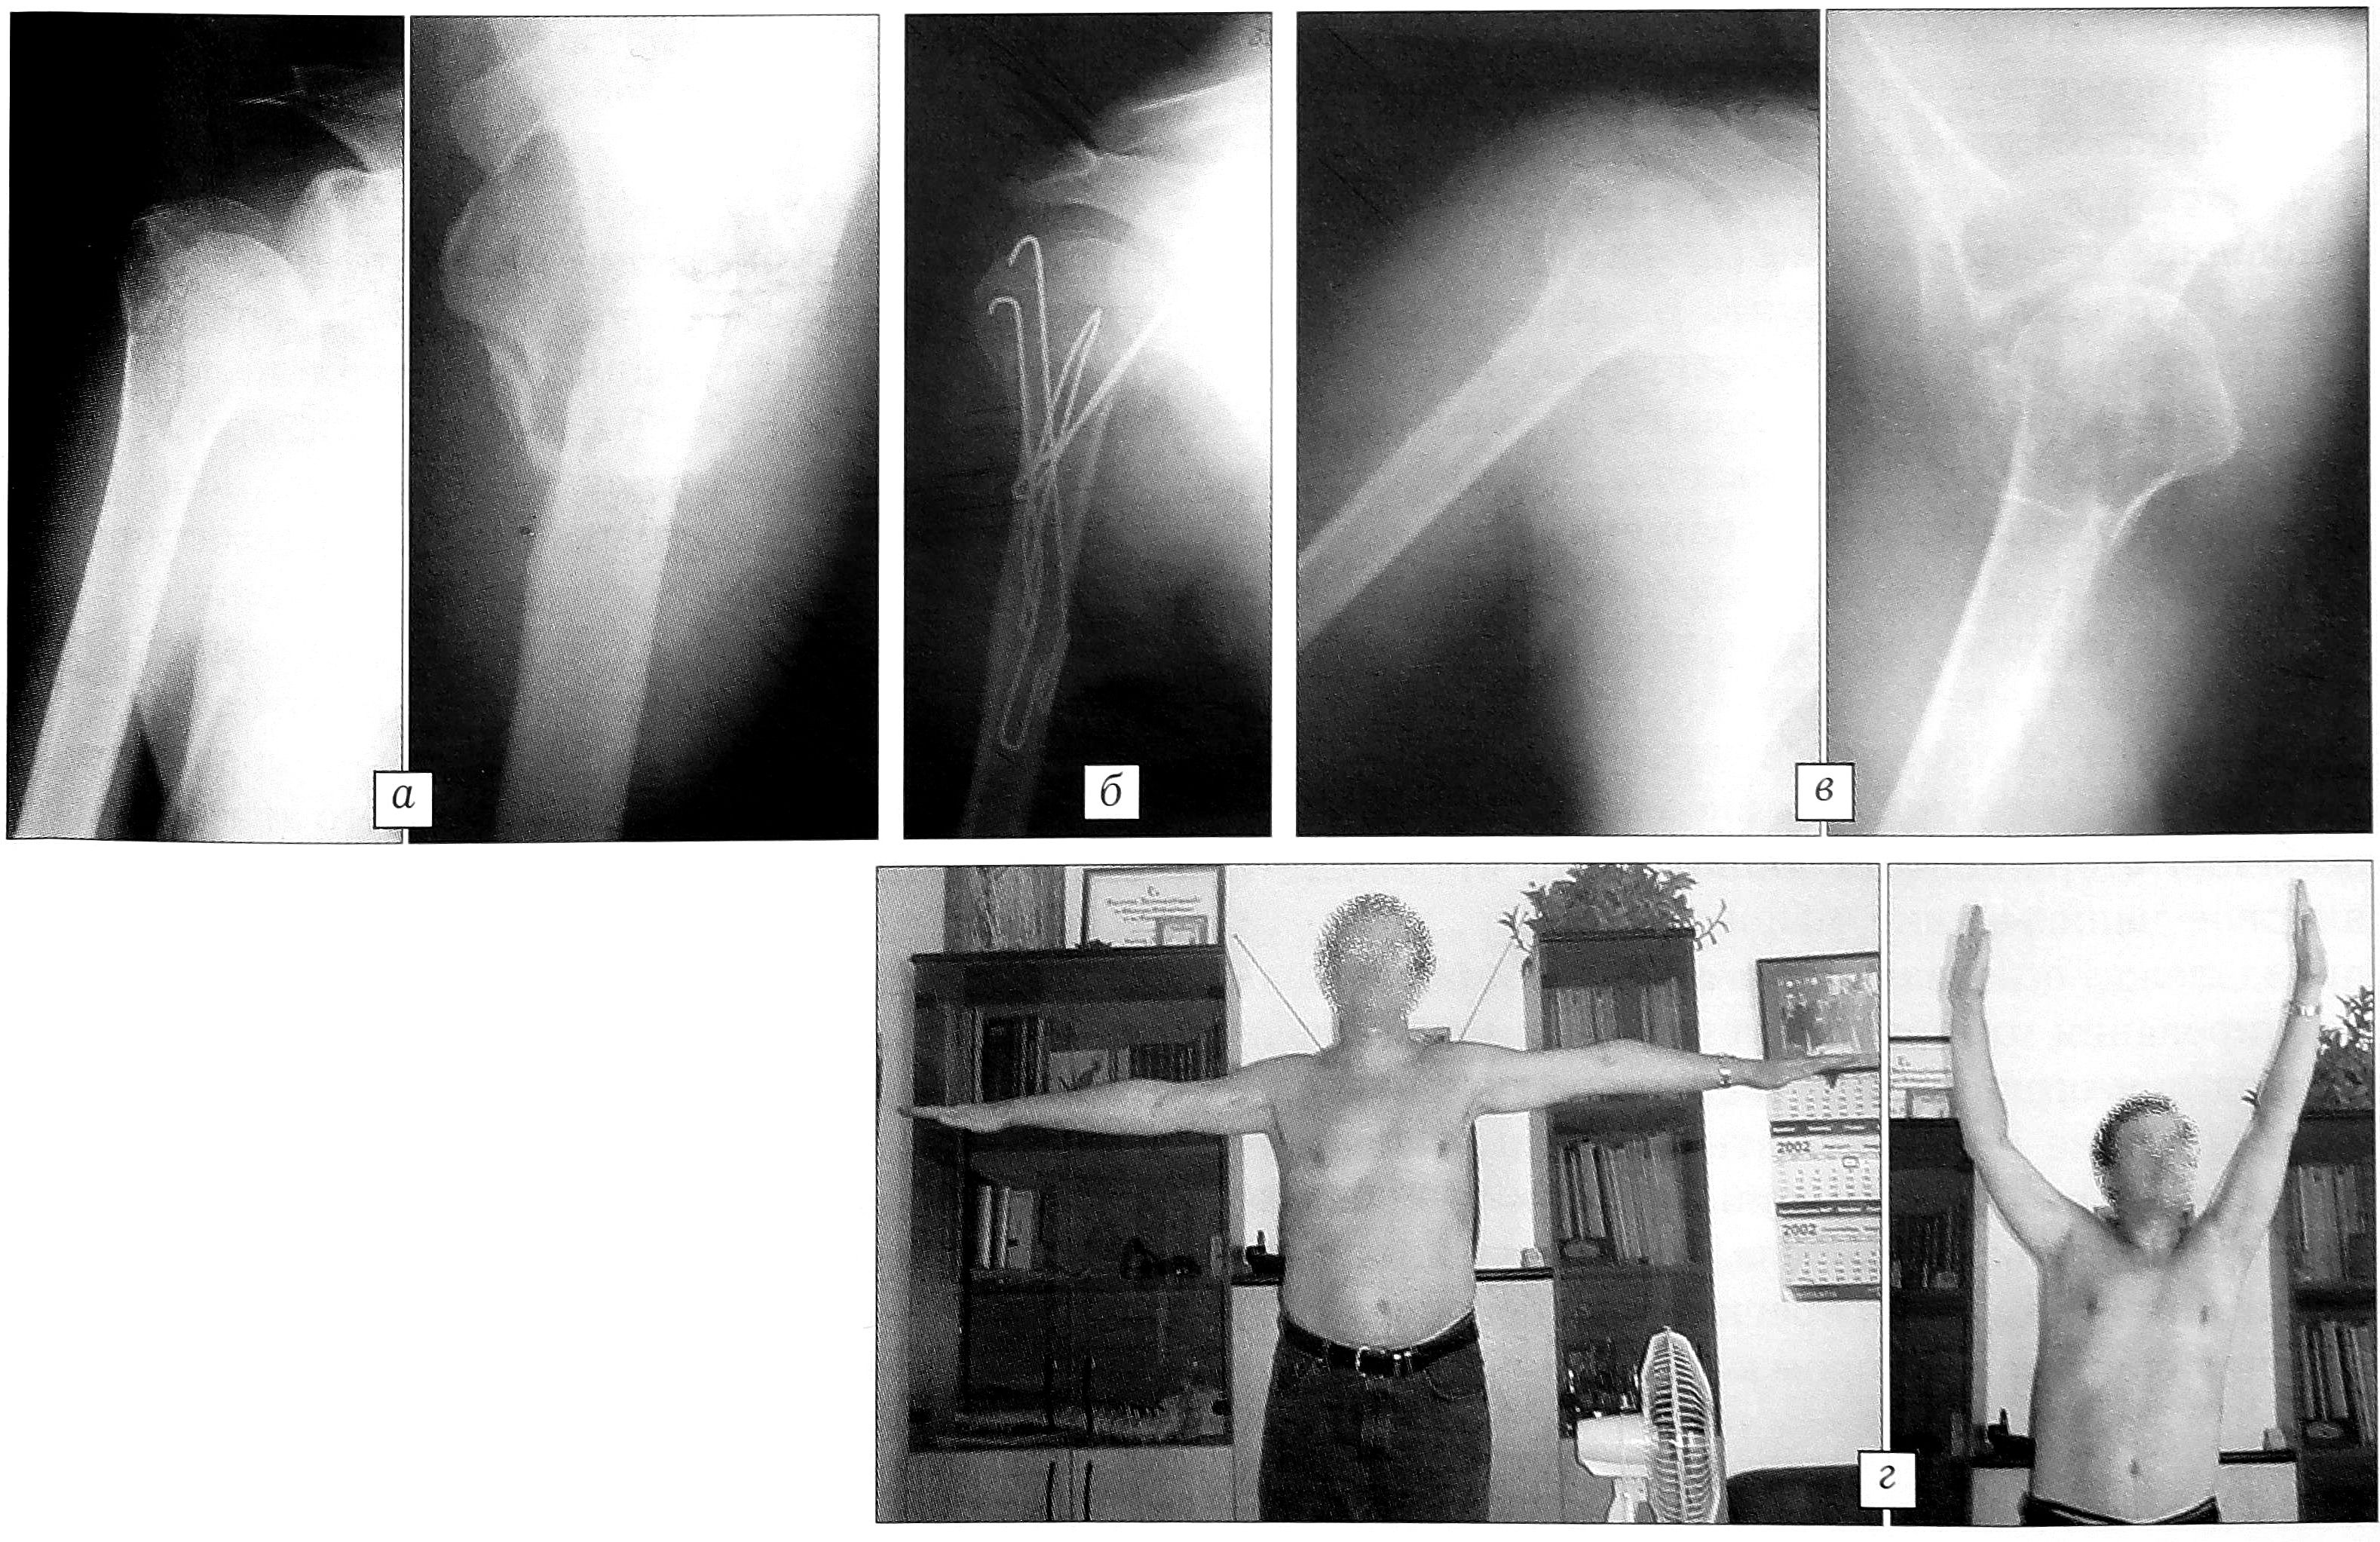

Больная Б.,67 лет, госпитализирована на 2-й день после травмы: упала на улице на область правого плеча, получила двухфрагментарный перелом хирургической шейки правой плечевой кости со смещением отломков. В травмпункте по месту Жительства произведена анестезия места перелома, рука фиксирована мягкой поддерживающей повязкой. В связи с усилением болевого синдрома и прогрессирующим ухудшением функции руки пострадавшая госпитализирована в ЦИТО. На 2-й день после поступления выполнены закрытая репозиция отломков и остеосинтез двумя напряженными Y-образными спицами. На следующий день после операции начаты активные занятия лечебной гимнастикой с разработкой движений в плечевом суставе. Отмечено значительное уменьшение болевого синдрома. Дополнительная внешняя иммобилизация после остеосинтеза не применялась. Швы с раны сняты через 10 дней после операции, на 12-й день с момента госпитализации больная выписана на амбулаторное лечение с возможностью пользоваться поврежденной рукой для самообслуживания. При контрольном осмотре через 2,5 мес после операции: перелом сросся, функция плечевого сустава полностью восстановлена (рис. 3).

Рис. 3. Больная Б. 67 лет. Двухфрагментарный перелом хирургической шейки правой плечевой кости. а — рентгенограммы до операции; б — рентгенограммы после остеосинтеза Y-образными спицами; в — рентгенограмма через 2,5 мес: сращение перелома; г — функция плечевого сустава через 2,5 мес.